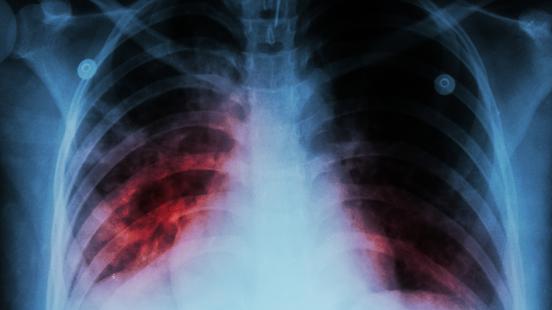

La tuberculosis está causada por la bacteria Mycobacterium tuberculosis y suele afectar los pulmones, pero también otras partes del cuerpo. Se transmite por el aire cuando las personas con TB activa en los pulmones tosen, estornudan o escupen. No se transmite por compartir utensilios para comer, dar la mano, abrazar, tocar la ropa de cama, el inodoro compartido, mantener relaciones sexuales o tener contacto con la saliva al besar a alguien.